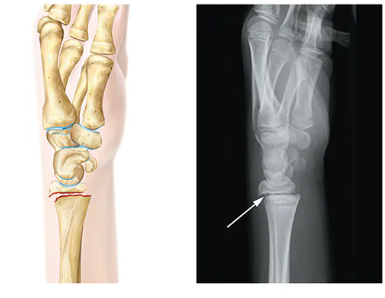

Avulsion